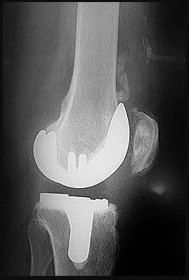

A 65-year-old man presents with anterior knee pain and a feeling of instability during stair climbing 1 year after a primary total knee arthroplasty.

Examination reveals a lateral patellar tilt. CT scan is performed to evaluate component rotation. Which of the following errors in component positioning is most likely responsible for his symptoms?

Explanation

Internal rotation of the femoral component or the tibial component increases the Q angle, leading to lateral patellar maltracking, lateral patellar tilt, and anterior knee pain. External rotation of the components generally improves patellar tracking.